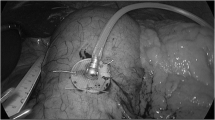

It has been interesting that most interventions in the field of bariatric surgery or endoscopy have been made without detailed attention to underlying potential mechanism of action. The potential mechanisms for neurohormonal pathways that could be affected and utilized by EMACS have been discussed earlier. We have proposed the following animal protocol that would not only establish the safety of the device in an animal model but at least provide insight into possible mechanism of action. We are also aware that the cornerstone of our device, that is, incorporation of behavior modification to change eating habits, will not be applicable in an animal model, especially swine. However, the swine stomach is similar in size and shape to a human stomach. The pig anatomy makes it ideal for magnetic capture and the distance from skin to gastric wall is ~5 cm [57]. Pigs in the 20–50 kg range have been used in previous bariatric studies [58]. Mini pigs will be used to determine feasibility of placement, durability, and removal of the device. Also, the mini pigs will be used to determine the proposed efficacy of the device by monitoring the effect of the device on pig growth, weight, and the impact on GI hormones involved in satiety. Mini pigs weighing 20 kg at the onset of the study on a feed to grow diet normally weigh 50 kg after 6 months. The rationale for mini pigs is shorter stature and shorter distance between their abdomen and the ground, allowing for the use of external magnets at the bottom of a special cage (Fig. 19.12).

At specific hours each day, individual pigs will be taken to special individual experimental cages (Fig. 19.12) where they will be fed twice daily. The cage is designed so the pig is relatively immobile. The magnetic simulation will be done by the technician using an external magnet under a clear plexiglass floor. The size, height, and distance of the external magnet will be adjusted according to pig size to simulate magnetic pressures comparable to a human subject by rubbing an external magnet on the surface of the abdomen. Different sized cages corresponding to different time intervals in the study will be used.